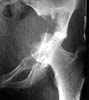

A female 22 years old admitted with the hip protrusion. Xrays are 12 months apart. Biopsy doesn't confirm malignization. What surgery can be done here? Is there any chance of primary hip replacement?

I think you need to get the opinion of a musculoskeletal oncologist, but it appears that this patient has an aggressive giant cell tumor and will likely require an aggressive wide excision. As a result reconstruction will be difficult.